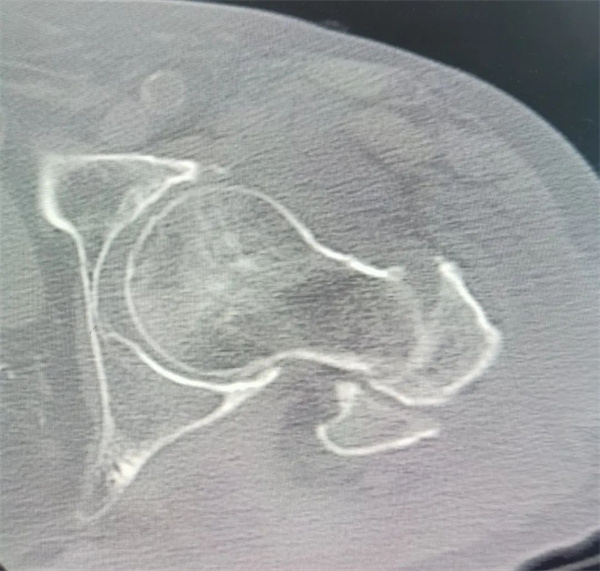

今年已92岁高龄的林奶奶于7月在家中不小心跌倒,当时自觉左髋剧烈疼痛,无法起身。家属急忙背起林奶奶送至市二医院急诊科就诊。接诊医师对其进行了耐心细致的检查,发现林奶奶除了左股骨粗隆骨折之外,还合并有家属搬运患者方式不当导致的多处肋骨骨折,慢性支气管炎,肺部感染,重度骨质疏松,脑梗塞后遗症,高血压3级极高危,同时存在重度贫血。老人基础病众多,全身状况差,病情危重。施行手术,麻醉难度极大,手术风险较高。

▲术前影像资料